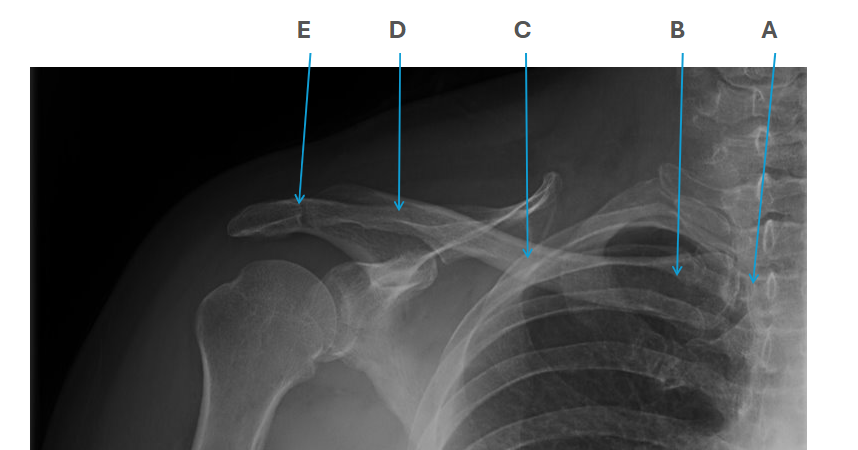

what is clavicle A

SC joint

what is clavicle B

sternal end

what is clavicle C

shaft/body

what is clavicle D

acromion

what is clavicle E

AC joint